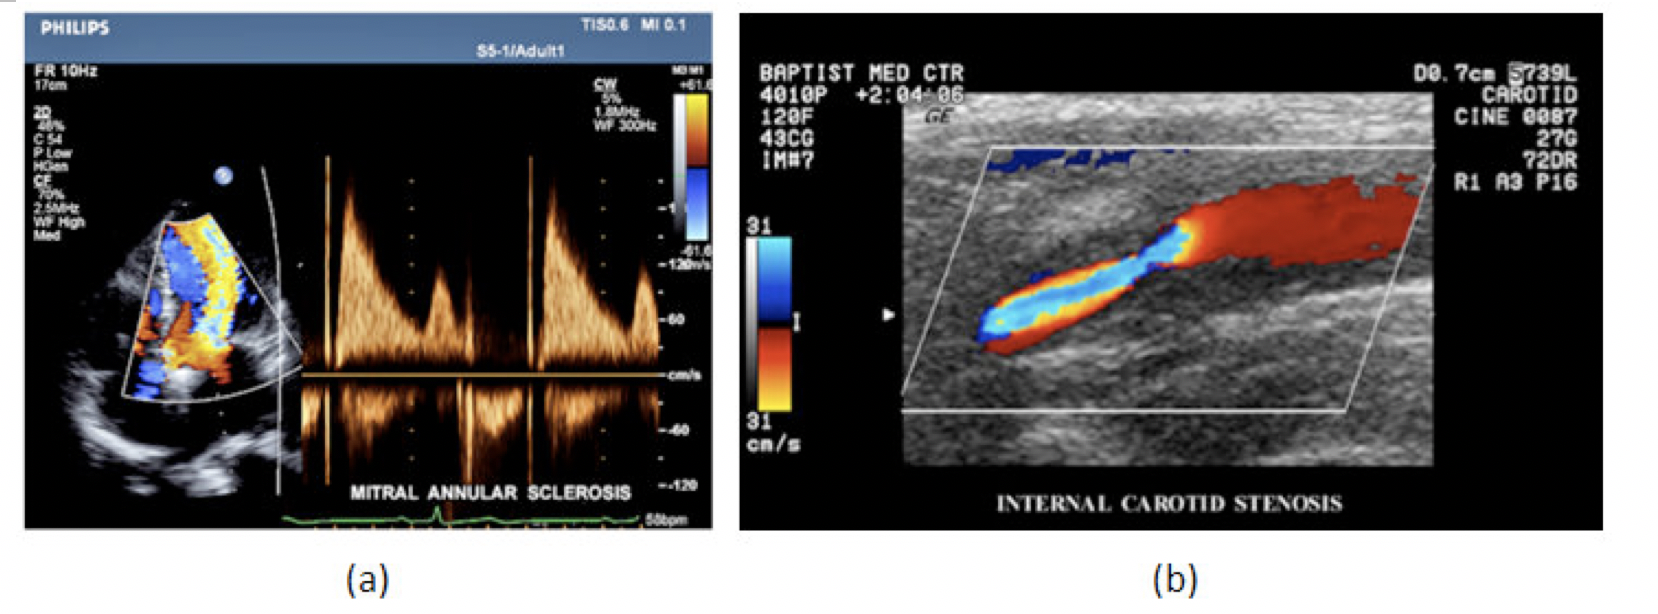

在CW和PW多普勒模式中,流信息是从一个聚焦声束中获得的,类似于A模式成像。在20世纪80年代,研究人员基于彩色多普勒技术完成了血流分布的二维信息可视化。彩色多普勒处理也是基于B模式/PW模式信号路径。从感兴趣区域收集多帧RF数据。由于感兴趣区域中的血液流动导致图像帧之间存在数据差异。相域中的自相关和时域中的互相关两种算法可从RF数据中提取数据方差(即血流速度和方向信息):。根据预定义的颜色渐变条相应地映射包括速度和方向的血流信息。通常,蓝色和红色代码分别识别朝向和远离换能器移动的血流。当流速增加时使用更亮的颜色,反之亦然。颜色映射的2D分布始终叠加在B模式图像上,以实时同时显示个体解剖结构和血流。它对于诊断心血管疾病,如血管闭塞和心脏瓣膜反流,极其有用。典型的彩色多普勒图像如下图所示,(b)显示颈动脉狭窄引起的血流流速变化。

图7.彩色多普勒成像:(a)以彩色多普勒和CW模式获得的图像(由Philips提供);(b)显示颈动脉狭窄的彩色多普勒(由GE提供)